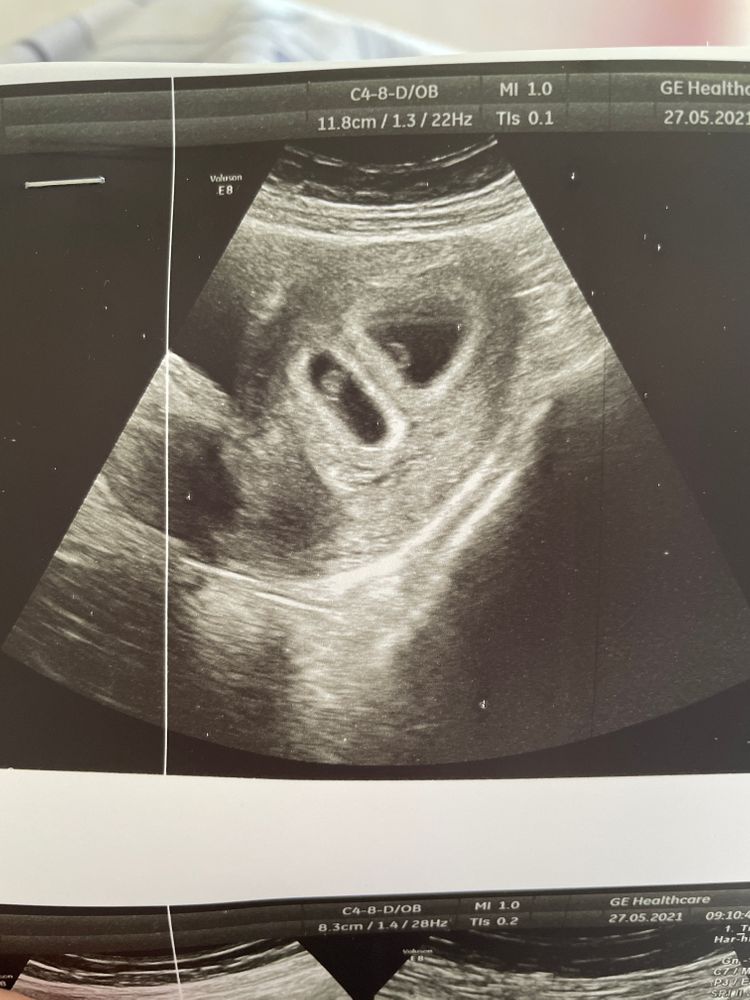

Мне сделали эко с 50% скидкой, ( все правда и реально, хотя я думала будет подвох до последнего) все получилось с первого раза, 2 карапуза решили остаться со мной. Вчера 29 дпп на узи 2 ПЯ, 2 эмбриона и у каждого бьется сердечко 😍🙏🏻